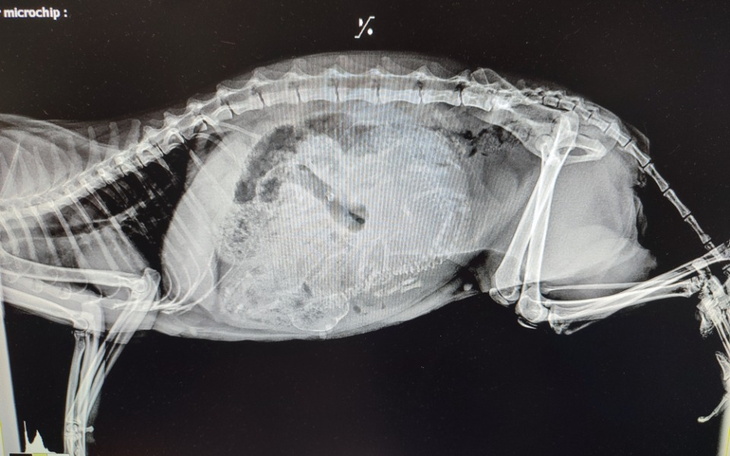

W gabinecie przy badaniu brzuszek był twardy z początku podejrzewano płyn w brzuszku. Zamarłyśmy - pierwsza myśl FIP... Weterynarz stwierdził jednak że nie jest to typowy brzuch przy FIPie i że wyczuwa coś innego. Zrobiliśmy USG i ku zdziwienia wszystkich weterynarz zaobserwował serduszko... Kolejne badanie RTG, które wykazało obecność co najmniej 3 maleństw... Podsumowując: kotka w zaawansowanej ciąży...

Kotka na dniach będzie rodzić. W tak zaawansowanej ciąży nie jesteśmy w stanie zrobić aborcji.